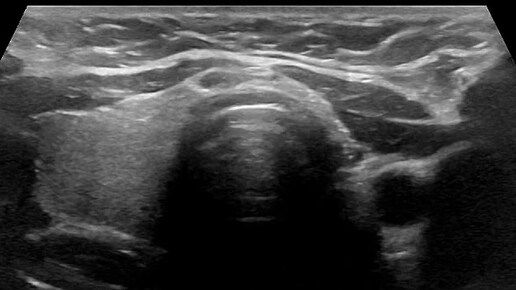

Видео к статье "Аплазия доли щитовидной железы"Адрес: https://dzen.ru/a/aBhLHPV5_mqxaPN7

Ультразвуковые находки от врача УЗД Зорина Я.П.